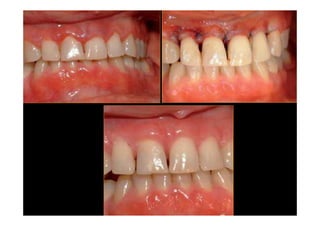

SUBGINGIVAL

CURETTAGE

BEFORE AND

FOUR WEEKS

AFTER

PROCEDURE